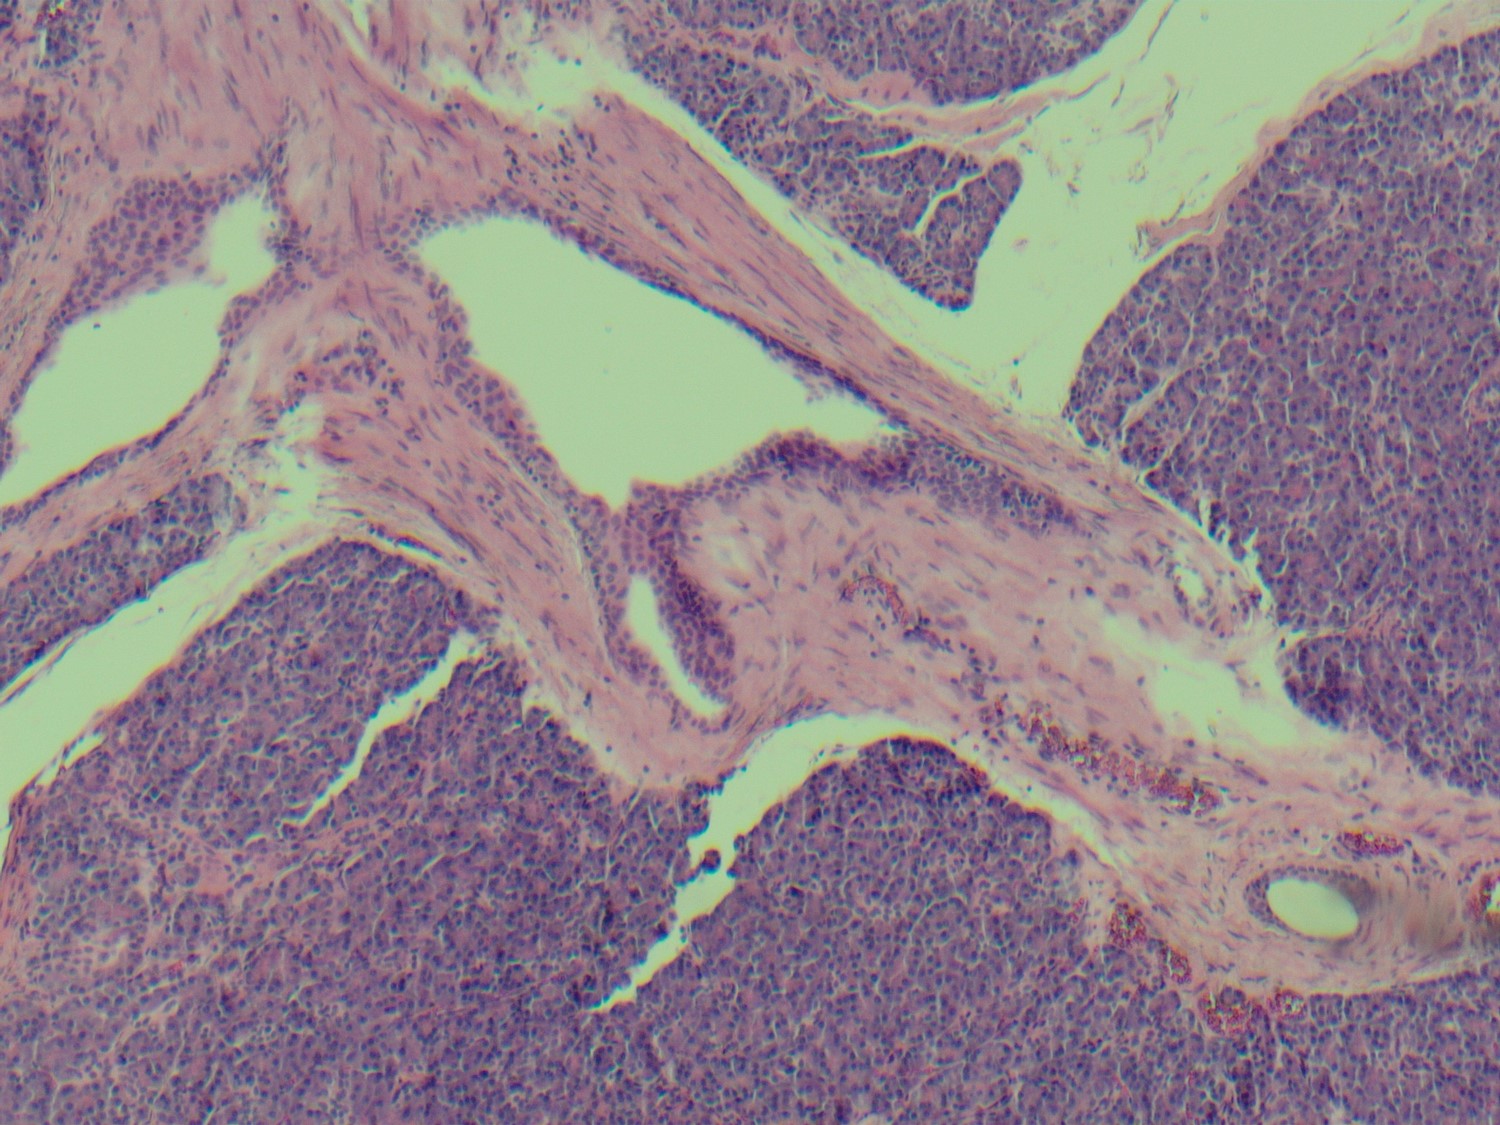

The lesion was resected, showing a submucosal rest of histologically normal pancreatic parenchyma (Fig 5-7).